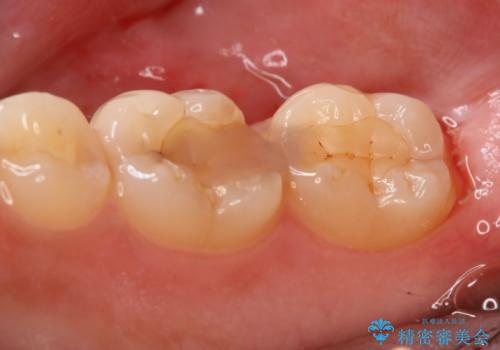

切削量・形態を考慮し、セラミックインレーでの治療を計画しました。

- 154000円(2本分)費用は治療当時の料金となります

虫歯が深い場合、痛みなどの症状が出る可能性がありますが、経過は良好でご本人も満足されています。